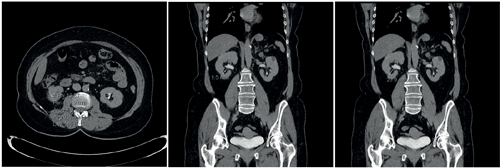

Figure 1b. 635HU, lower pole stone with a narrow (1.5mm) and long (21mm) infundibulum.

The maximum SSD varies according to the lithotripter in use and its specific focal length; but studies generally point to an SSD<10cm as appropriate. Although ESWL can treat (i.e. fragment) stones in all calyces, those within the lower pole have the lowest rate of clearance (25%). The intra-renal anatomy affects this further, with a wide (>5mm), short (<10mm) infundibulum, with a shallow infundibulo-pelvic angle (>70o) allowing better clearance of fragments than if the stone is at the end of a tight, long infundibulum.

Hounsfield unit density can be used as a guide to the stone’s ‘hardness’, with various studies giving different cut-off values for predicting success. Hard stones (calcium oxalate monohydrate, or the ‘Brushite’ form of calcium phosphate stones) fragment less readily and therefore are more likely to cause obstruction on travel or indeed may not fragment at all. Ouzaid et al. evaluated the outcome four weeks after ESWL by non-contrast computed tomography (NCCT) and found that patients whose stones had a Hounsfield unit density <970 had a stone-free rate (including “clinically insignificant residual fragments ≤4mm”) of 96%, but this was just 38% if the stones HU density was ≥970HU (P<0.001) [15]. Furthermore, various parameters can be combined to give even more precise prediction of stone-free rates: using a combination of stone density <600HU, skin-to-stone distance <12cm and stone volume, Tran et al. demonstrated a likelihood of being stone free increased from 21.4% (if all parameters were unfavourable) to 96.1% if all were favourable [16].